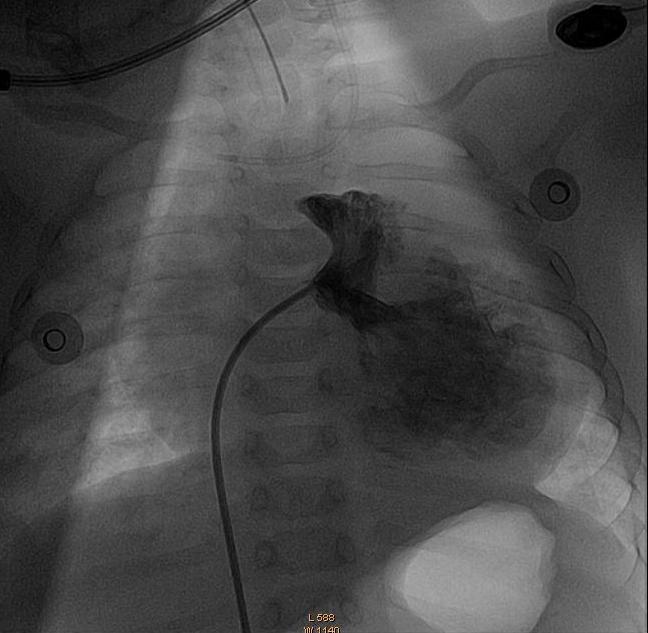

Fig 2- ..."Con ello

lo que podemos visualizar que se concentra la mayor cantidad en la auricula

derecha"...

| Fig 5 -..."Se realiza una nueva inyección con lo que se verifica la corrección del defecto de forma temporal"... |